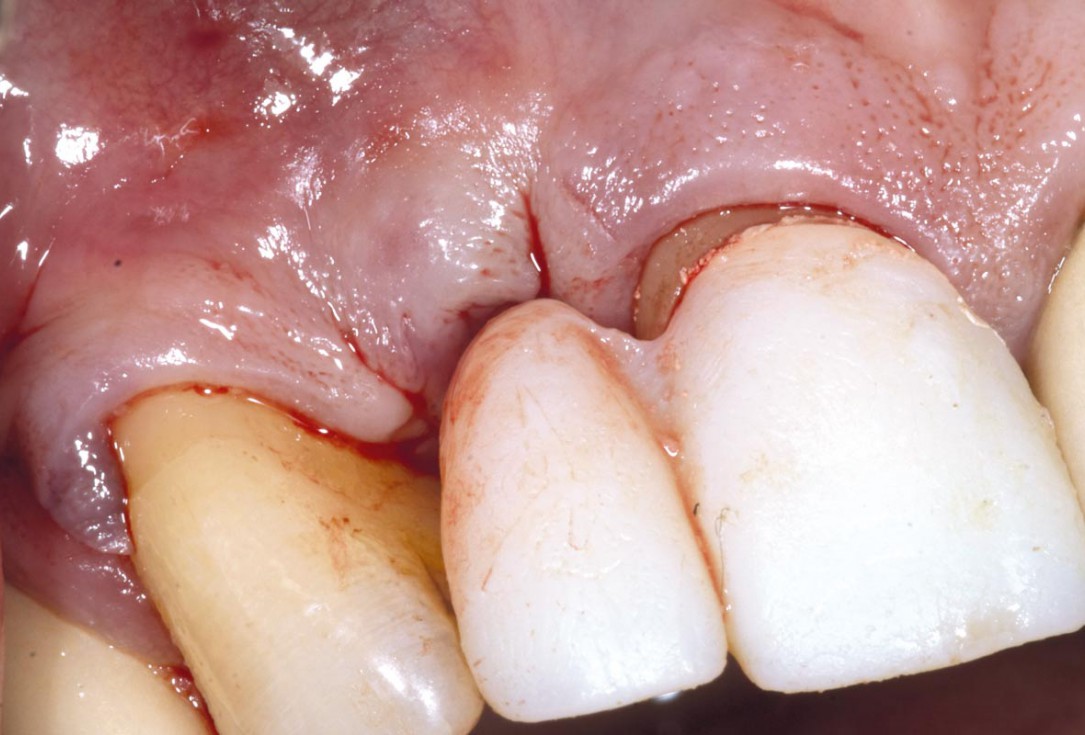

1/19 - Initial situation: Inflammated tooth #12Bone augementation with maxresorb® - Dr. R. Cutts

Initial situation: Inflammated tooth #12